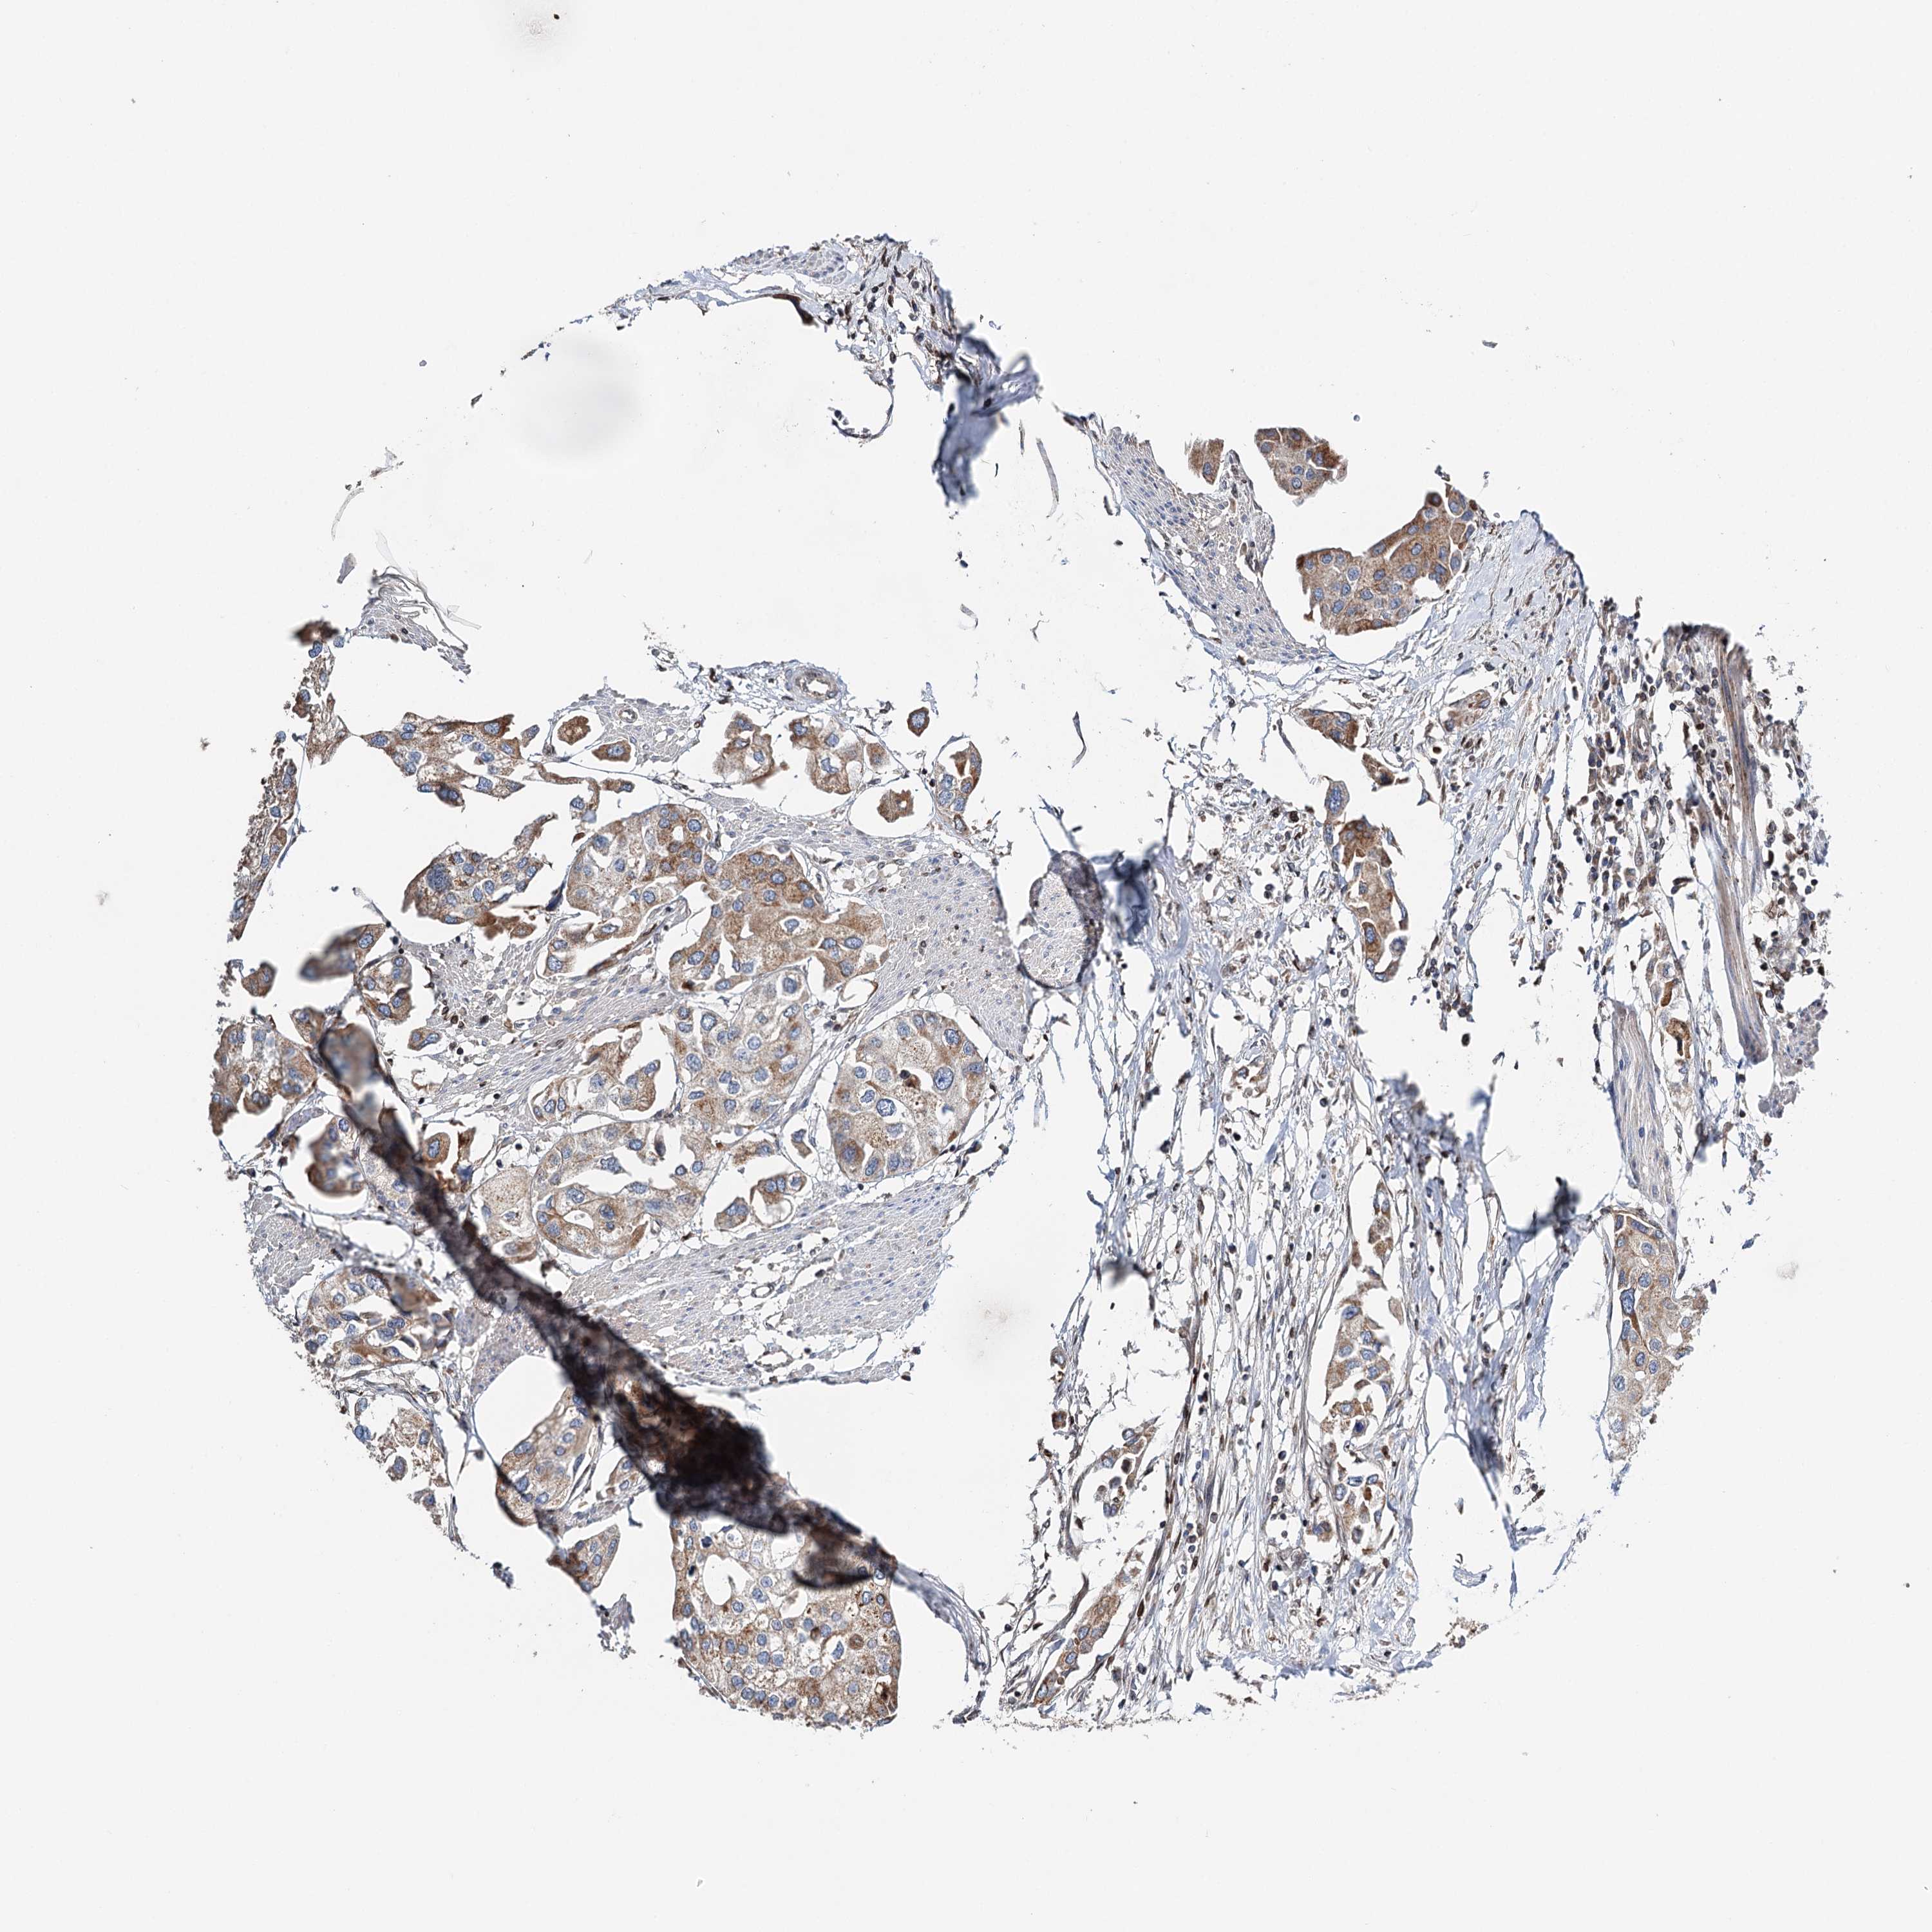

UROTHELIAL CANCER - Protein expressioni

A mouse-over function shows sample information and annotation data. Click on an image to view it in a full screen mode. Samples can be filtered based on level of antibody staining by selecting one or several of the following categories: high, medium, low and not detected. The assay and annotation is described here.

Note that samples used for immunohistochemistry by the Human Protein Atlas do not correspond to samples in the TCGA dataset.

Antibody stainingi

Antibody staining in the annotated cell types in the current human tissue is reported as not detected, low, medium, or high, based on conventional immunohistochemistry profiling in selected tissues. This score is based on the combination of the staining intensity and fraction of stained cells.

Each image is clickable and will lead to virtual microscopy that enables deeper exploration of all samples and also displays staining intensity scores, fraction scores and subcellular localization as well as patient and tissue information for each sample.

Antibody HPA037786

Antibody HPA038034

Antibody HPA038867

Antibody HPA038868

Staining

High

Medium

Low

Not detected

Intensity

Strong

Moderate

Weak

Negative

Quantity

>75%

75%-25%

<25%

None

Location

Nuclear

Cytoplasmic/membranous

Cytoplasmic/membranous,nuclear

Urothelial carcinoma, High grade

Urothelial carcinoma, Low grade

Urothelial carcinoma, NOS